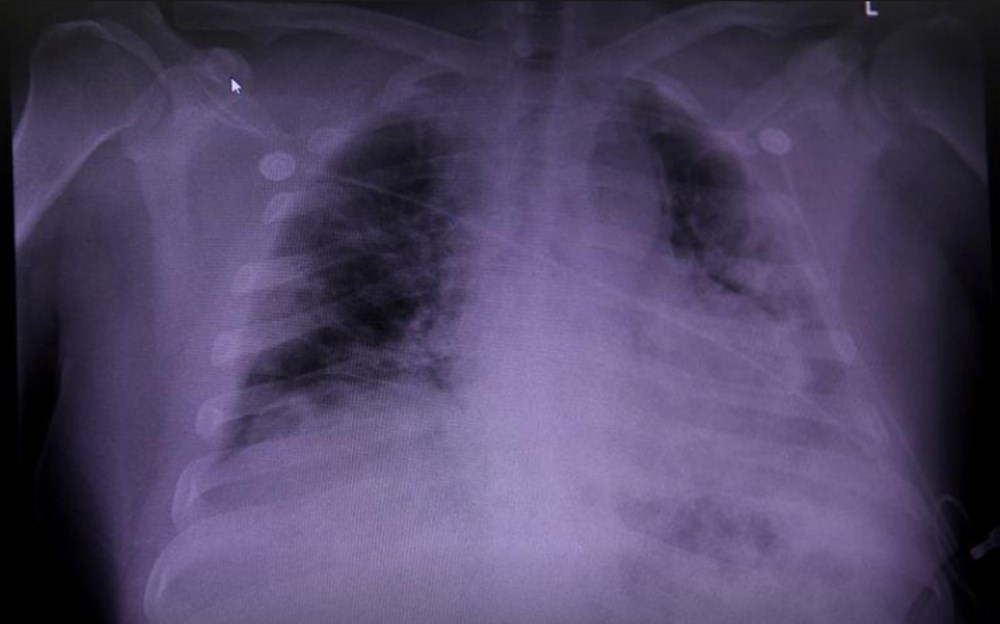

Covid-19'dan ölenlerin organları analiz edildi.Neler değişmiş?

Semptomların sekiz hafta ya da daha uzun sürmesiyle, “uzun süreli Covid-19” durumu ortaya çıkıyor.

İngiliz bilim insanları, corona virüsün akciğerlerde yarattığı tahribat ile uzun süreli Covid-19 arasındaki ilişkiyi inceledi.